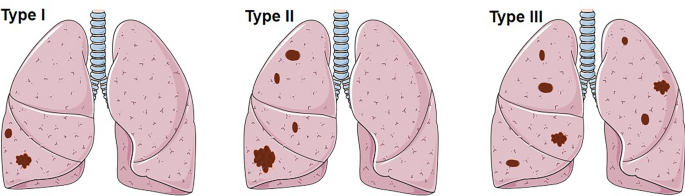

Patients with multiple PSP generally require a CT examination of the chest for its detection. Imaging analysis of 36 patients with multiple PSP revealed the maximum lesion diameter to range from 6 to 226 mm (median [interquartile range]: 27.5 [20, 50] mm; mean ± SD: 43.54 ± 46.18 mm). This is larger than the average diameter of solitary PSP patients (mean: 43.54:30.56 mm), but there is no statistical difference between the two groups. With regard to the distribution of tumor locations, some scholars14 classified them into five different subtypes, such as “Type I: a dominant SP (Sclerosing pneumocytoma) with satellite nodules that occur in one lobe (multi local); Type II: SPs that are distinct, separate fractions in the same love; Type III: SP occurring in different ipsilateral lobes; Type IV: SP occurring independently in central lobes and Type V: SP occurring bilaterally in all lobes”. After analysis, this classification method is considered to be relatively cumbersome and to have no clinical guiding significance in diagnosis and treatment. Therefore, the distribution of tumor locations is simplified into three types: I, multiple PSP located in a single lung lobe; II, multiple PSP located in multiple lung lobes of the unilateral chest; and III, multiple PSP located in multiple lung lobes of the bilateral chest (Figs. 2, 3). An analysis revealed that type II multiple PSP was more, approximately 44.44%, followed by type III multiple PSP (36.11%), whereas type I multiple PSP was relatively less (19.44%). This classification method can better guide the clinical treatment strategy of multiple PSP. An analysis of the imaging findings of multiple PSP revealed 8.33% of patients to have lymph node metastasis or even extrapulmonary metastasis15, which was significantly higher than the lymph node metastasis rate of solitary PSP17,18,19,20.

The site of multiple PSP.

The subtypes of multiple PSP. Type I: multiple PSP located in a single lung lobe; Type II: multiple PSP located in multiple lung lobes of the unilateral chest; Type III: multiple PSP located in multiple lung lobes of the bilateral chest.